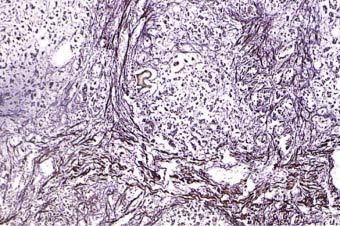

Microscopy showed the complete loss of the normal hepatic architecture, with massive parenchymal destruction and collapse of the reticulin framework (Fig. 13.15). The residual hepatocytes were disposed as nodules, displaying variable cellular regeneration and ballooning degeneration, within extensive areas of densely fibrous stroma (Fig. 13.16). There was florid ductal proliferation and mild to moderate, mixed inflammatory infiltrates, containing T-lymphocytes (CD3+, CD20−). Prominent focal cholestasis, mostly intracannalicular and intraductal in distribution, was present (Fig. 13.17). Excessive copper or iron deposition was not seen. These features were deemed to be consistent with repair and limited parenchymal regeneration following upon massive hepatocellular necrosis.

Fig. 13.15.

Case #6: The liver microarchitecture showing collapse of the reticulin framework (Gordon & Sweet’s ×100)